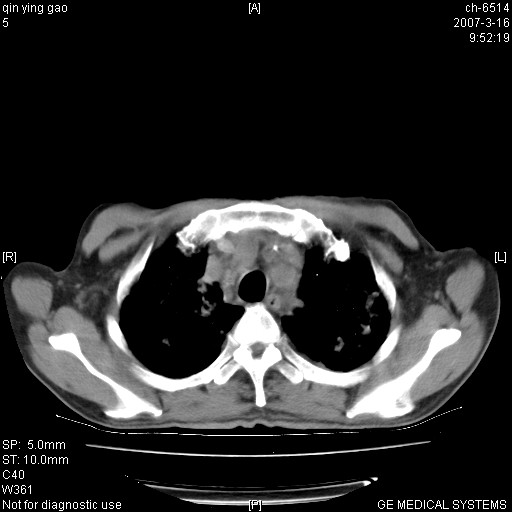

男,64岁.乏力2个月,畏寒、发热1月余。体重下降。血沉加快,白细胞不高。

双肺以中上肺野为著斑片状.结节壮密度增高影 左上肺前段可见小类圆钙化灶 纵隔淋巴结无明显肿大

3.主动脉弓.冠状动脉钙化形成

两肺弥漫分布的斑片状影,部分融合,左肺及纵隔淋巴结见钙化影,考虑1。tb,2。肺泡细胞癌,建议查痰检

病变以两肺上野为著,部分病灶有钙化,纵隔窗显示病灶有新老不一,这个首先和结核脱不了干系,还有部分病灶有融洽的倾向,肿瘤也不能完全排出